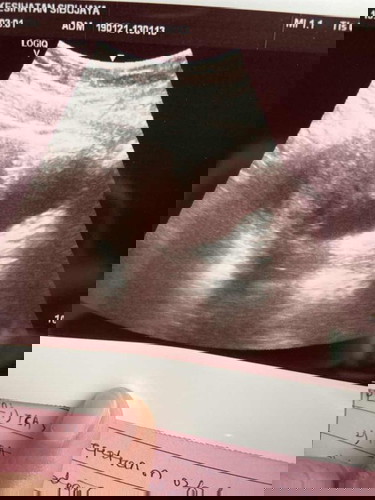

5 weeks baby scan but still cant see baby

Hai yalls. last week i go to med checkup to clinic and dr scan for my baby, she said the baby are still cant be seen. is it normal? sorry this is my first experience pregnant

Saya pun 5w5d scan belum nampak kantung lagi. Scan ke-2 kali masa 8weeks baru nampak kantung. Nanti week 10 baru doctor scan lagi untuk cek heartbeat.